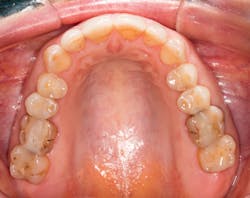

A patient presented with multiple deficient restorations, discolored teeth, and attrition (figures 1–4). The patient’s treatment plan was a full-mouth rehabilitation with a combination of veneers, crowns, and onlays.